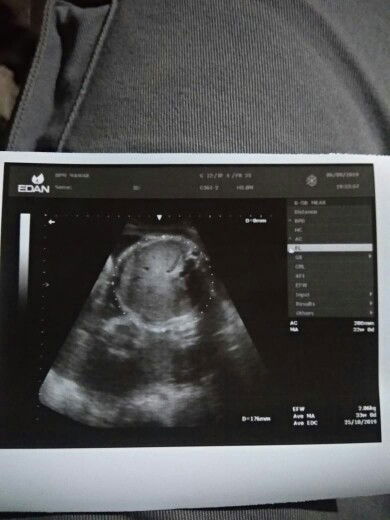

USG anak pertama ku ?

Dede tersayang sebentar lagi akan lahir ke dunia?? jadi pelengkap kebahagian ayah dan bunda ???